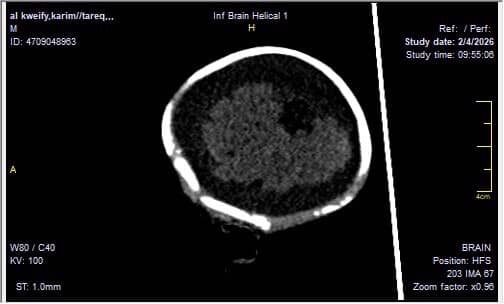

A 3-month-old baby in my family is facing a life-threatening brain condition. Medical reports and imaging confirm serious neurological injury that requires immediate, specialized treatment outside Gaza—care that is not available here.

Without urgent medical intervention, this baby is at high risk of:

• Permanent brain damage

• Severe developmental delays

• Seizures and lifelong disability

• Or loss of life